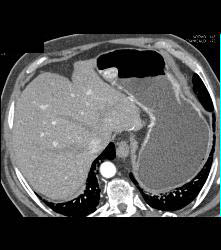

Glomus Tumor